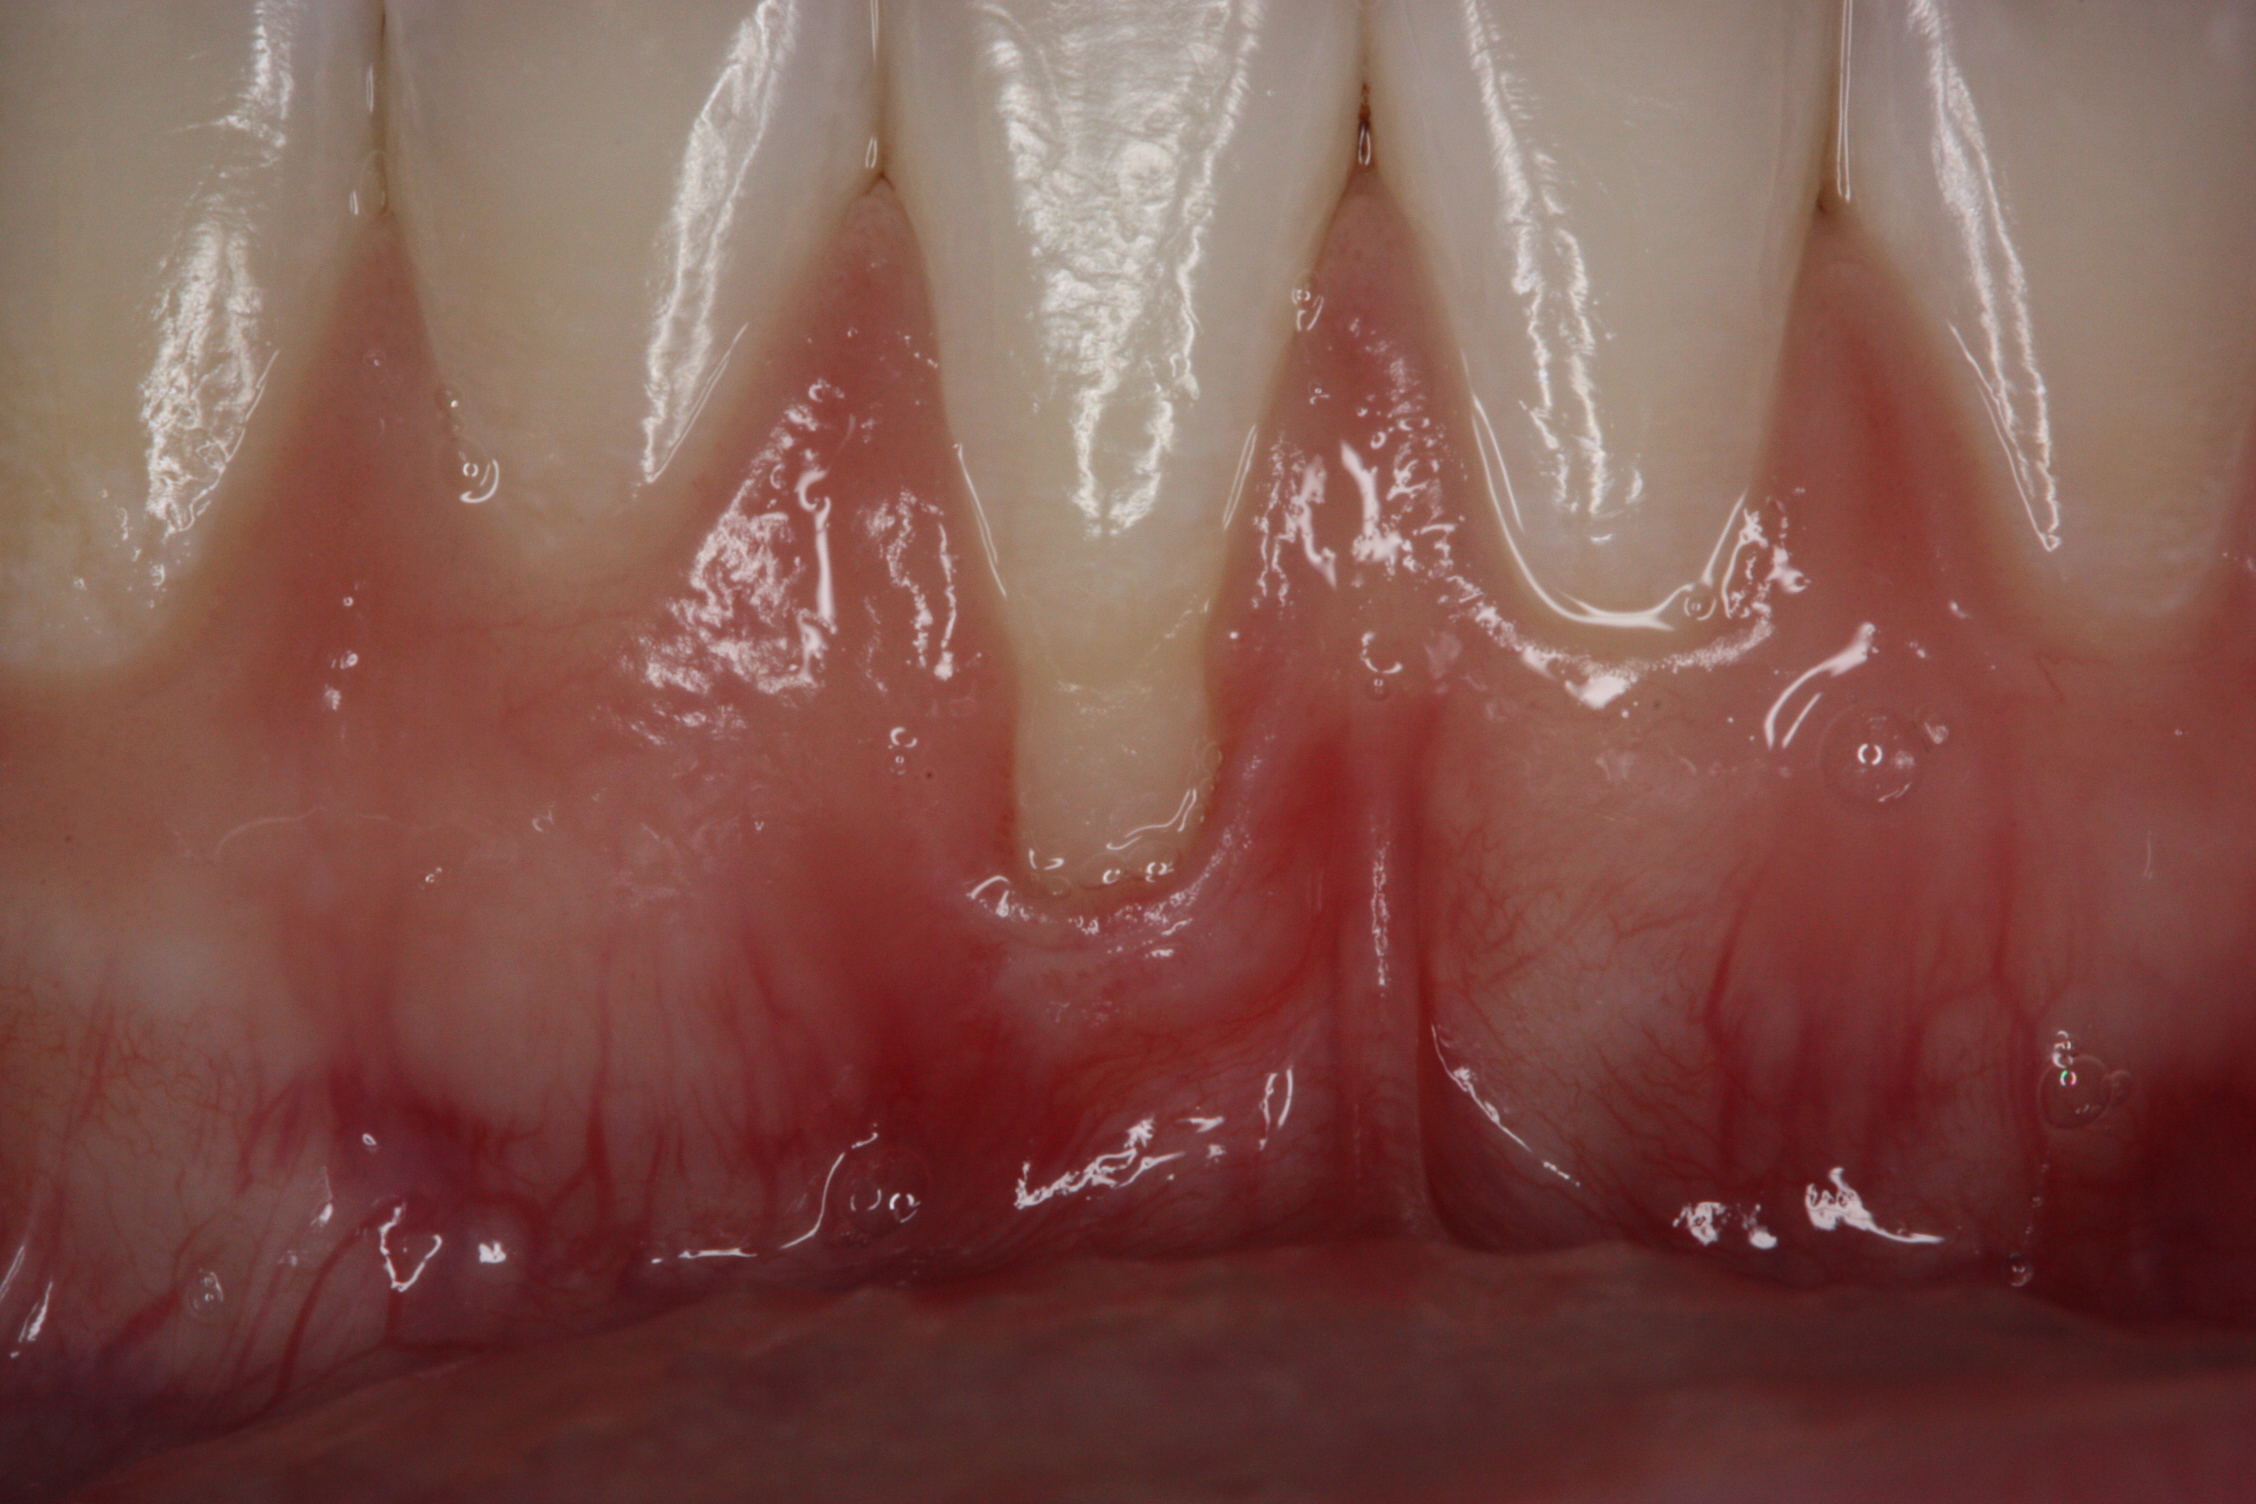

Fig 6. Pretreatment clinical view, maxillary left anterior sextant, of case presented.

Figure 6

A 24-year-old, nonsmoking man presented for correction of gingival clefting and recession in the maxillary left anterior sextant (Figure 6). The patient’s medical history was noncontributory. After consultation and presenting various options to the patient to correct the localized recession, the patient opted for the use of acellular dermal matrix tissue rather than harvesting tissue from his palatal area.